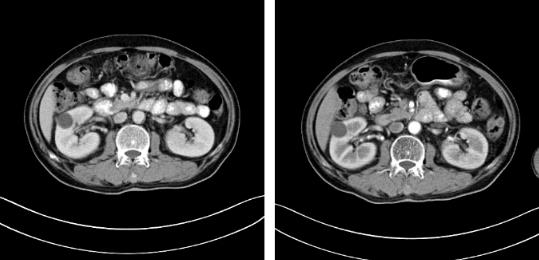

随着时间的推移,安图叔叔身体开始发生明显变化,腰疼的症状得到缓解,血尿的次数明显减少,睡眠质量有明显的改善。以前上厕所都是一件很痛苦事情,如今逐渐正常。安图叔叔的病情得到改善,在一次次的复查中得到主治医生王峰的佐证。过去的两年里,安图叔叔一直遵循医生的嘱咐,按时服药定时回院复查,到目前为止是安图叔叔第9次来院复查。安图叔叔的儿子说道:“我每次带父亲来检查都有新发现,肿瘤在一天天的变小,我们很相信医生的话,他们会给我们最好的治疗方案,如今已过去两年,父亲身体和精神慢慢转好,这是我们所希望的。”

自2017年做冷冻消融术后,安图叔叔两年多时间肿瘤不仅没有增长并多次检查没有复发迹象。安图叔叔认为,冷冻给他带来新的希望,又一次看到复大创造新的奇迹。